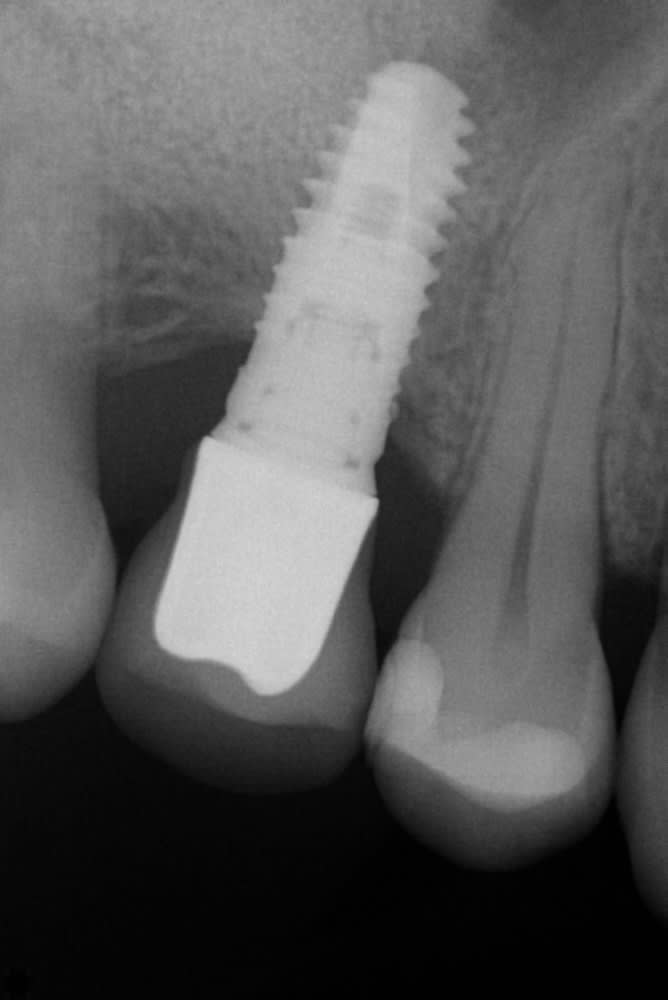

Un patient se présente a ma consultation pour une couronne sur implant qui bouge.

Est ce que quelqu'un pourrait m'aider pour son identification?

Xive S friadent 100% sûr (sauf du diamètre)

https://whatimplantisthat.com/implants/details/xive-s-plus-2